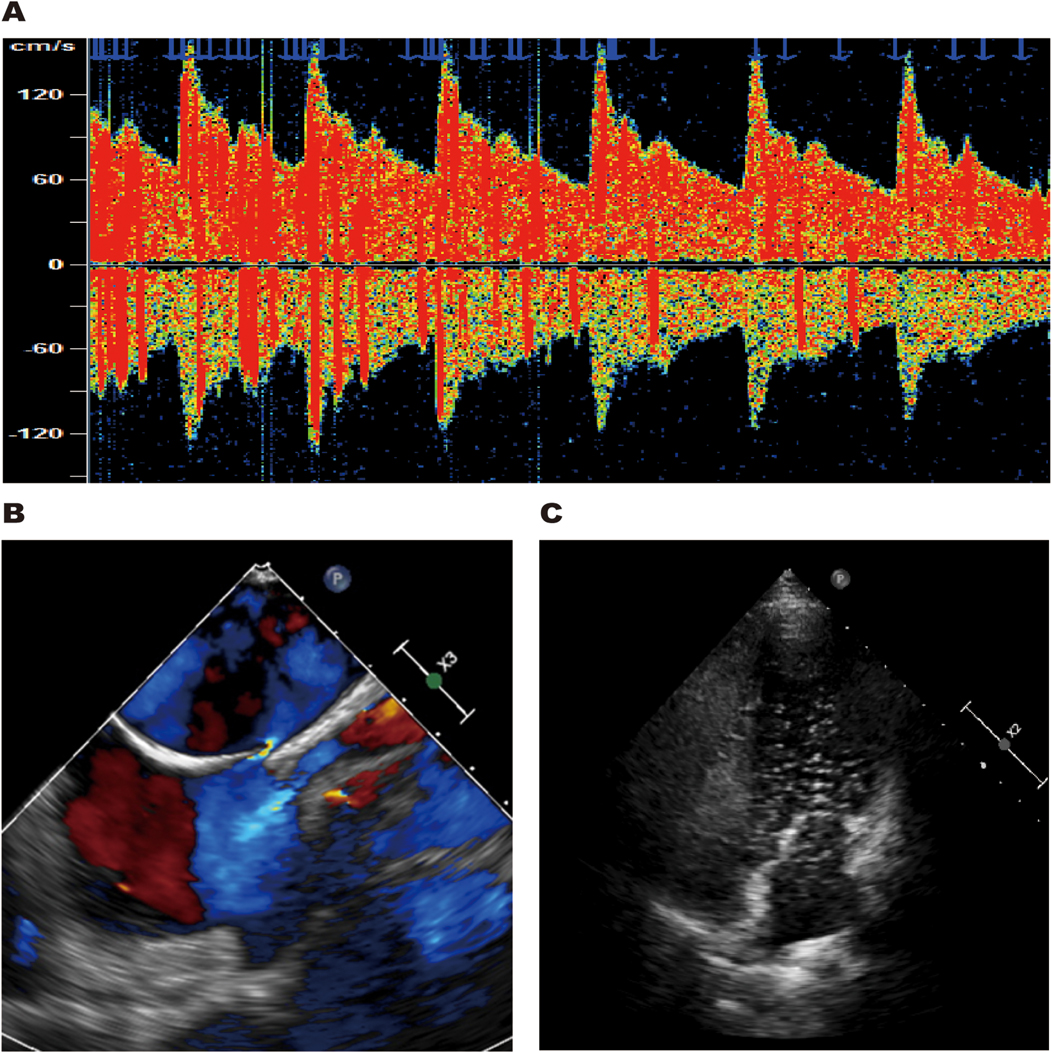

The patient had no traditional cerebrovascular risk factors, and her RoPE score was 9. Therefore, we conducted a comprehensive cardiac evaluation to rule out the possibility of paradoxical embolism. Doppler bubble study demonstrated >25 microbubbles (Grade 3 right-to-left shunt) during the Valsalva maneuver, displaying the characteristic “shower-curtain” pattern (Figure 4A). Further transesophageal echocardiography (TEE) showed the primary and secondary septa of the atrial septum were separated by approximately 2.7 mm, indicating a patent foramen ovale (Figure 4B). Agitated saline contrast echocardiography (ASCE) showed moderate microbubble passage into the left atrium at rest, markedly increasing during the Valsalva maneuver (Figure 4C), confirming significant intracardiac right-to-left shunting.

Figure 4

TCD bubble study revealed a grade 3 right-to-left shunt during the Valsalva maneuver (A). TEE showed the primary and secondary septa of the atrial septum were separated by approximately 2.7 mm (B). ASCE revealed large microbubble passage into the left atrium during the Valsalva maneuver (C).